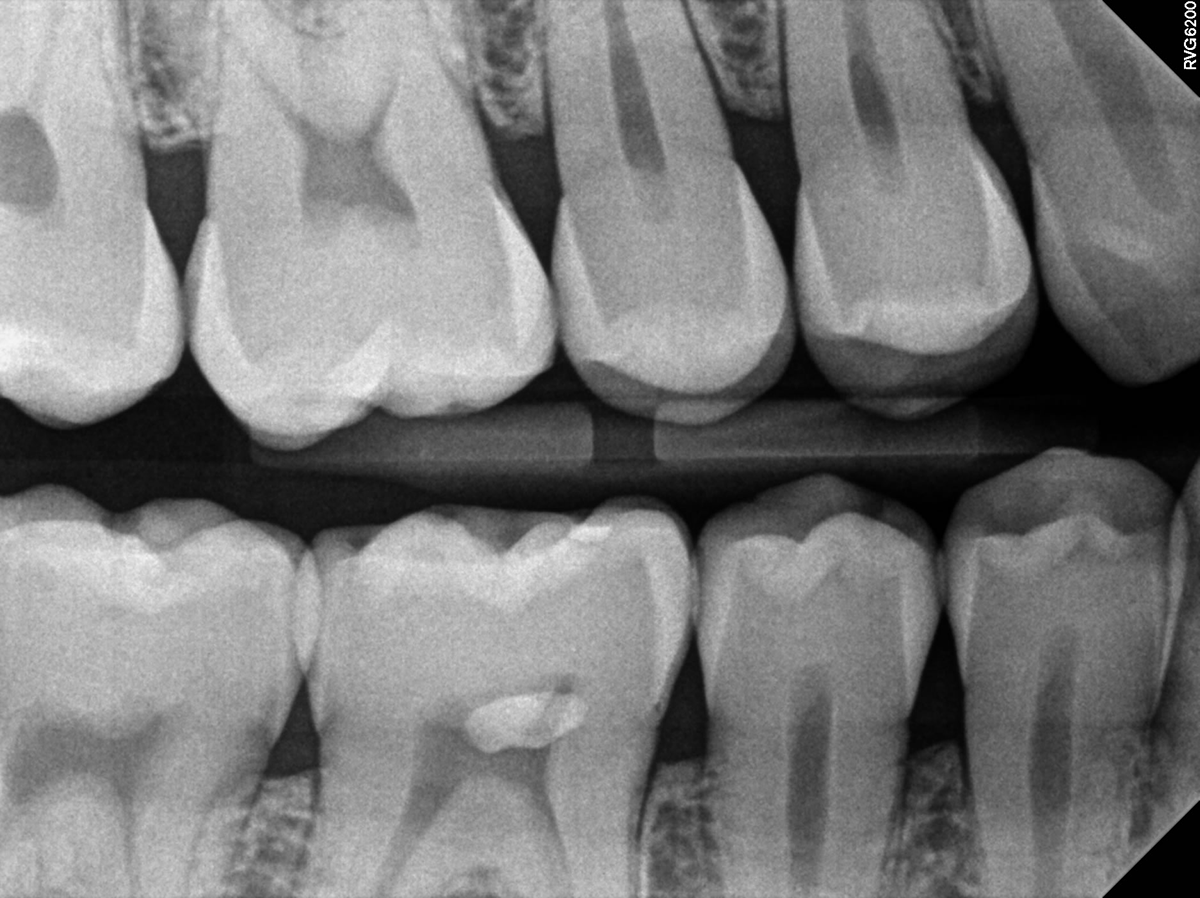

- Bitewing – depistează cariile dintre dinţi si ocluzale, fisuri ale smalţului

- Carii incipiente, ce pot fi tratate foarte uşor

- Amploarea reală a cariei care la suprafaţă pare mică

- Carii aflate sub lucrări sau plombe

- Fisuri ale smalţului